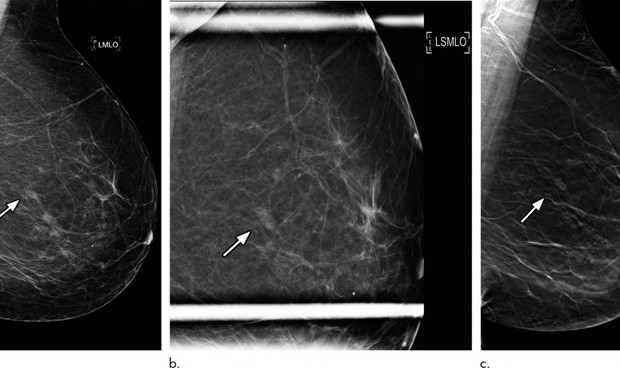

Imagen de una radiografía de mama.